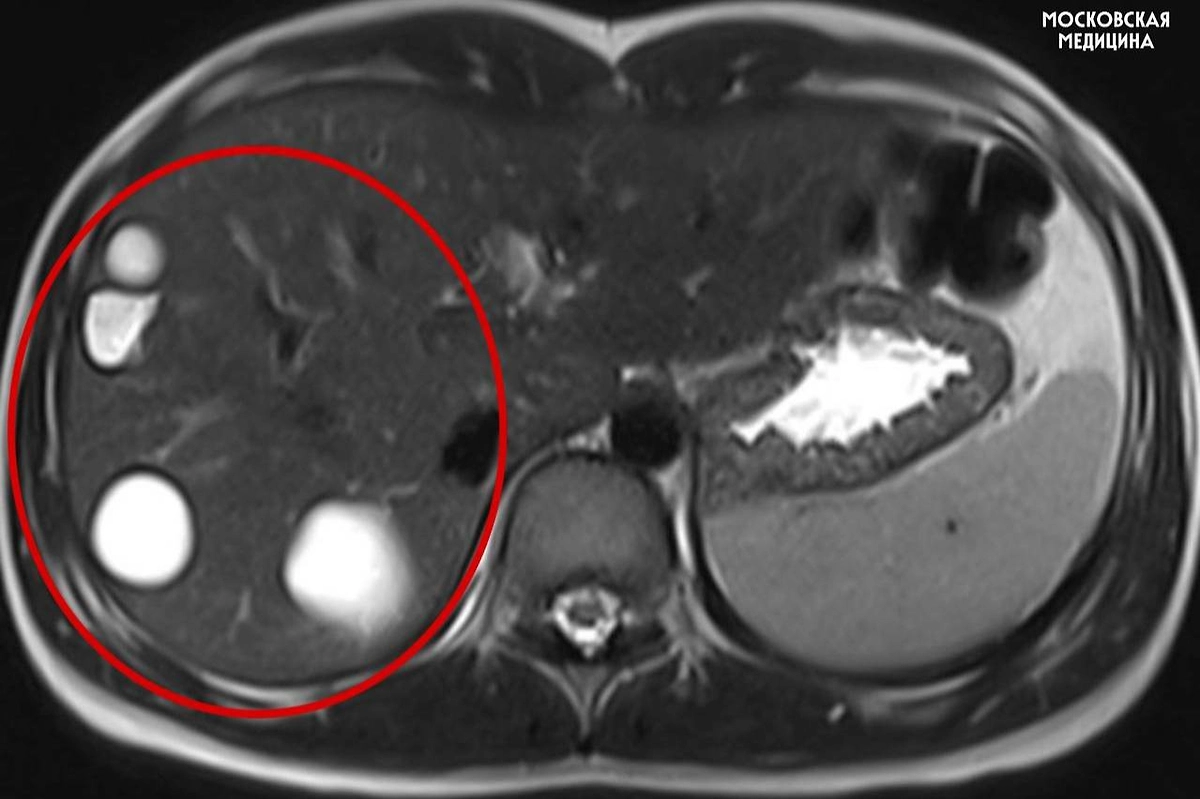

В столичной больнице имени Сперанского врачи спасли 14-летнюю девочку, у которой случайно обнаружили сразу несколько паразитарных кист печени. Находку сделали во время обычного планового обследования — никаких ярко выраженных симптомов у ребёнка не было. После диагностики школьницу сразу направили на операцию. Об этом рассказали в московском департаменте здравоохранения.

Как рассказал заведующий хирургическим отделением профессор Игорь Хворостов, эхинококкоз чаще всего выявляется поздно, так как его признаки — боль, лёгкая температура, тяжесть в животе или аллергия — выглядят неспецифичными. Хирурги провели лапароскопическую операцию и удалили пять кист. Уже через пять дней после вмешательства пациентку выписали домой.